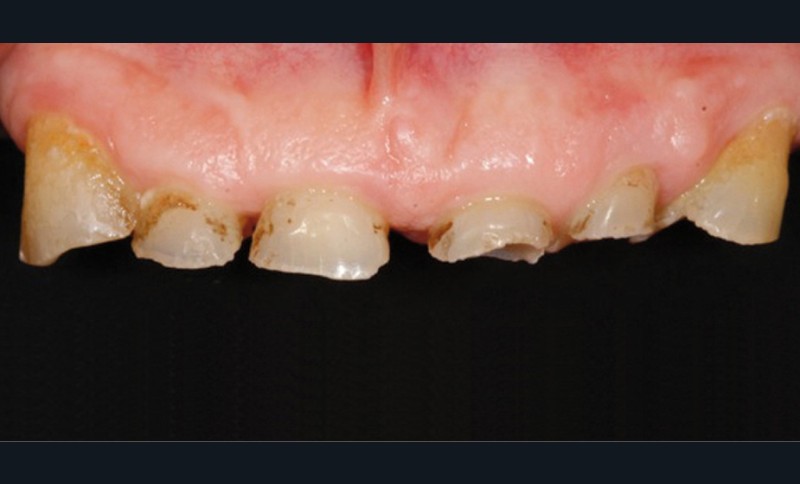

• L’examen intrabuccal montre de nombreux édentements non compensés (14, 15, 16, 24, 25, 26, 27, 47 et 36) ainsi que des pertes de substance très importantes, notamment dans le secteur antérieur.

• Le bilan esthétique nous indique plusieurs points disgracieux :

– dysharmonie des contours gingivaux (ligne des collets) avec une ligne du sourire basse [1] ;

– perte de substance extrême du bloc incisivo-canin maxillaire et des incisives mandibulaires ;

– visibilité très limitée des dents lors d’un sourire forcé ;

– égressions compensatoires.